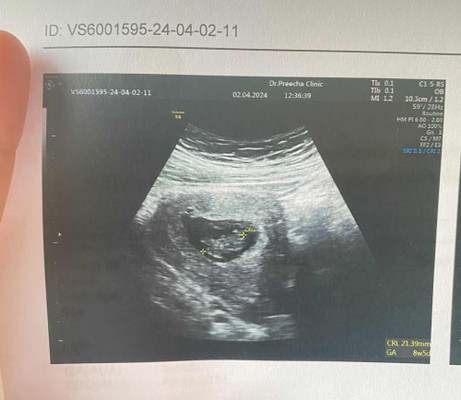

น้องน้อยได้ 8w5d แล้วค่ะ วัดความยาวน้องได้ 21.39 mm คือ2เซนใช่ไหมค่ะ ตามเกณฑ์ไหมค่ะ